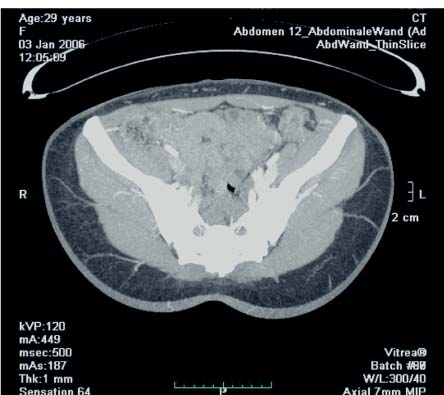

We recently started using multidetector computed tomography (CT) during the preoperative planning of perforator flaps ( Fig. 6.55 ). This modality has clear advantages over Doppler and duplex imaging. It can provide a highly detailed depiction of the perforating vessels, including their intramuscular portion. The caliber can be assessed, as well as the subcutaneous branching patterns. A precise surgical plan can therefore be devised, taking into account the best perforator and alternatives, reducing the risk of intraoperative errors and minimizing operating time. Choosing the most remotely located perforator from the SGA pelvic exit point will provide a longer pedicle, making the insetting and shaping of the flap easier.